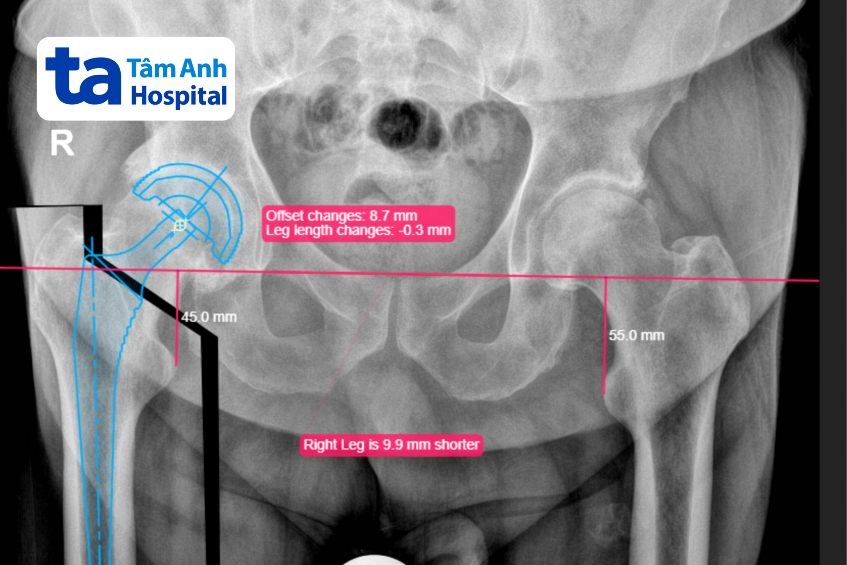

Ông Bruce có thể thực hiện các động tác như ngồi xổm, vắt chéo chân, không bị giới hạn trong sinh hoạt tình dục… “Với đường mổ ABMS và phần mềm TraumaCad chuyên dụng cho tính toán cấu trúc khớp, chúng tôi có nhiều lựa chọn cấu hình khớp phù hợp nhất với cấu trúc giải phẫu tự nhiên của người bệnh, giúp người bệnh đi lại, vận động tự nhiên như trước khi mắc bệnh”, bác sĩ Khoa nói.